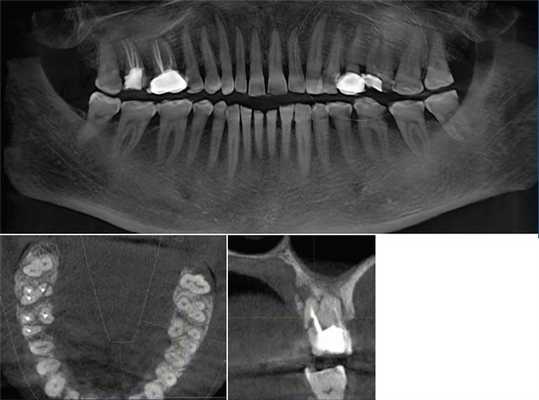

4. Панорамная томография

Более трех десятилетий назад в арсенал рентгенодиагностики заболеваний зубочелюстной системы, ЛОР-органов и других отделов черепа вошла панорамная рентгенография. При этом методе исследования аппликатор рентгеновской трубки вводят в рот пациента, а кассета располагается вокруг верхней или нижней челюстной дуги. В обоих случаях пациент придерживает кассету с наружной стороны ладонями, плотно прижимая ее к мягким тканям лица.

Проводится также и боковая панорамная томография, на боковом панорамном снимке одновременно отображаются зубы верхнего и нижнего ряда каждой половины челюсти.

Прямые панорамные рентгенограммы имеют преимущество перед внутриротовыми снимками по богатству деталями изображения костной ткани и твердых тканей зубов. При минимальной лучевой нагрузке они позволяют получить широкий обзор альвеолярного отростка и зубного ряда, облегчают работу рентгенолаборанта и резко сокращают время исследования. На этих снимках хорошо видны полости зуба, корневые каналы, периодонтальные щели, межальвеолярные гребни и костная структура не только альвеолярных отростков, но и тел челюстей. На панорамных рентгенограммах выявляются альвеолярная бухта и нижняя стенка верхнечелюстной пазухи, нижнечелюстной канал и основание нижнечелюстной кости.

На основании панорамных снимков диагностируют кариес и его осложнения, кисты разных типов, новообразования, повреждения челюстных костей и зубов, воспалительные и системные поражения. У детей хорошо определяется состояние и положение зачатков зубов.

5. Ортопантомография

Панорамная зонография, или, как ее чаще называют, ортопантомография, явилась своего рода революцией в рентгенологии челюстно-лицевой области и не имеет себе равных по ряду показателей (обзор большого отдела лицевого черепа в идентичных условиях, минимальная лучевая нагрузка, малые затраты времени на исследование).

Панорамная зонография позволяет получить плоское изображение изогнутых поверхностей объемных областей, для чего используют вращение рентгеновской трубки и кассеты.

Преимуществом ортопантомографии является возможность демонстрировать межчелюстные контакты, оценивать Результаты воздействия межчелюстной нагрузки по состоянию замыкающих пластинок лунок и определять ширину периодонтальных путей.

Ортопантомограммы демонстрируют взаимоотношения зубов верхнего ряда с дном верхнечелюстных пазух и позволяют выявить в нижних отделах пазух патологические изменения одонтогенного генеза.

Особенно важно использовать ортопантомографию в детской стоматологии, где она не имеет конкурентов в связи с низкими дозами облучения и большим объемом получаемой информации. В детской практике ортопантомография помогает диагностировать переломы, опухоли, остеомиелит, кариес, периодонтиты, кисты, определять особенности прорезывания зубов и положение зачатков.